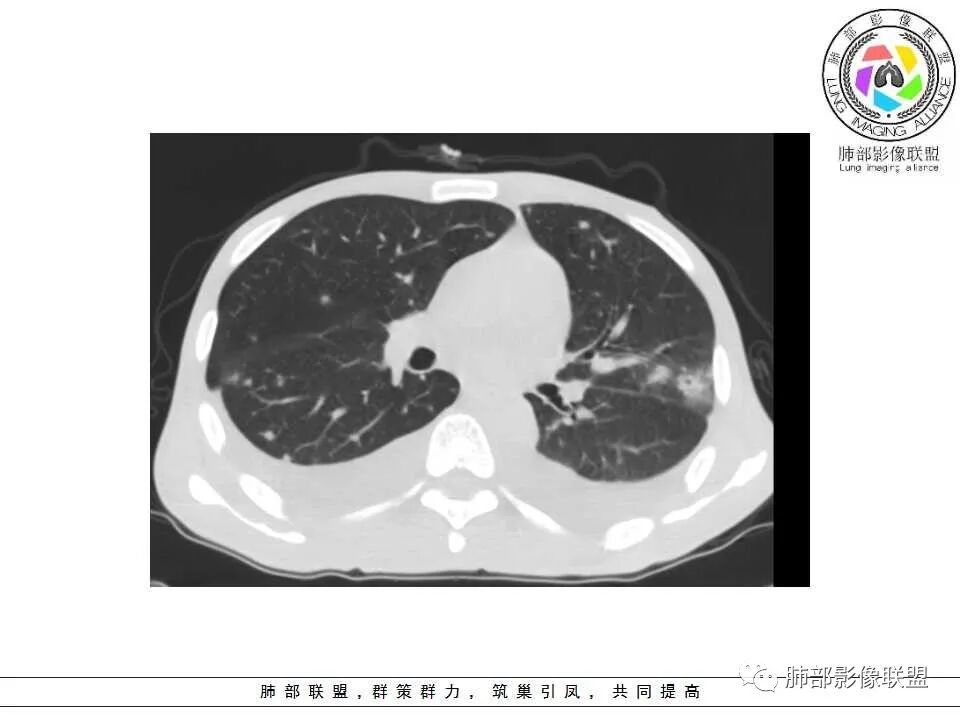

2.双肺散在不规则小片状影及结节影,部分可见磨玻璃晕。结节影边界较清楚。左肺片影边界不清,范围较大,支气管相关,支气管壁增厚不明显,病灶内见液化空洞。

4.脾脏明显增大,密度减低。肝脏未见异常密度影。

3.肺炎型肺部影像学表现常为双肺多发片影,肉芽肿样结节影,边界相对清楚,可见磨玻璃晕,部分病灶可显示坏死空洞。部分病例出现胸水。支气管炎型病例可见较广泛支气管壁增厚。

4.应当注意肺外组织器官病灶的发现,如肝脏多发小脓肿及脾脏多发低密度结节影等,出现于白念珠菌的这些肺外小脓肿颇具特色,可以类似转移瘤的“牛眼征”,宜结合临床及病史综合判断。